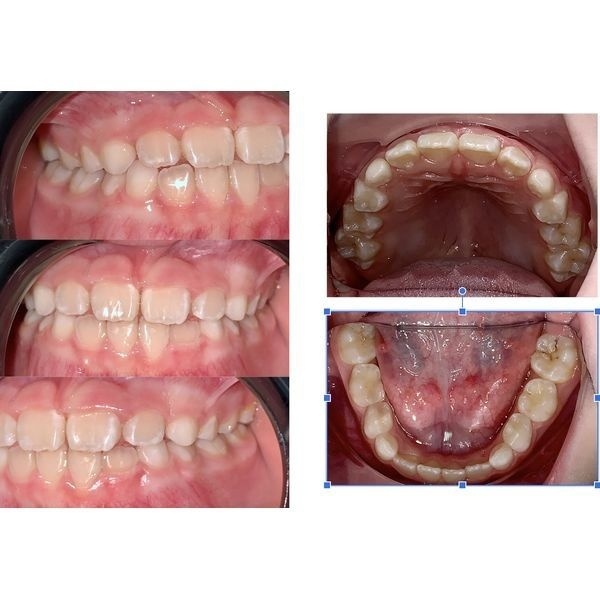

За довольно короткий срок прикус девочки изменился, а зубы 1.1 и 2.1 приняли естественное положение. Чтобы закрепить результат, ей рекомендовали надевать последний элайнер на ночь.

Заключение

Этот клинический случай показывает, что элайнеры крайне эффективны при лечении неправильного прикуса, при котором форма и размер челюсти соответствуют норме. При этом капы не создают никакого дискомфорта, а, наоборот, вызывают интерес у детей, так как каждая капа помещена в индивидуальную ярко раскрашенную упаковку.